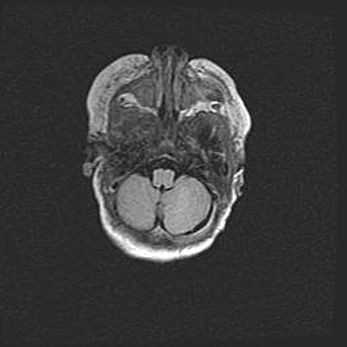

Церебральная ишемия II.

Возраст: 5 дней

Вес: 3400 г

Пол: женский

Окружность головы: 35 см

Срок гестации: 39 недель

Церебральная ишемия – это заболевание, характеризующееся недостаточностью (гипоксией) либо полным прекращением (аноксией) снабжения мозга кислородом по причине закупорки одного или нескольких сосудов. Это приводит к  что метаболическим расстройствам различной степени тяжести в тканях головного мозга, развитию коагуляционных некрозов и гибели нейронов.